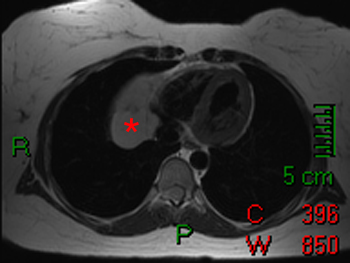

Pericardial cysts are congenital masses that are often located in the right cardiophrenic angle. These may appear as pericardiac masses on chest radiograph. Cardiac MRI can be useful in characterizing these lesions. On spin-echo imaging, they typically have a low intensity on T1-weighted imaging and homogenous high signal intensity on T2-weighted imaging. Lipomas are another benign lesion that sometimes arises from the pericardium; they typically have a high signal on T1-weighted imaging with loss of signal on fat saturated imaging.

These spin echo images demonstrate a pericardial cyst (*) adjacent to the right heart. The cyst is relatively low signal on the T1-weighted images (left) and relatively high signal on T2-weighted image (right).